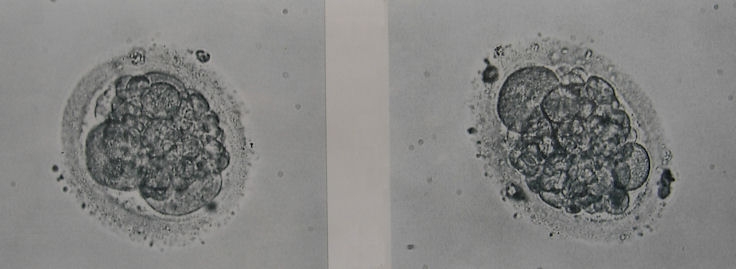

Laut meinen Recherchen im Internet wäre es D-Qualität mit vielen Fragmentierungen!?

In der Klinik wurde sich nicht weiter dazu geäussert, würde gern mal Ihre Beurteilung dazu hören!

Wieviel Zeller sind das?

Welche Qualität?

Zuviele Fragmentierungen?

Warum ist die rechte Zelle so oval?

ja, es sind schon deutliche Zeichen von starker Fragmentierung zu sehen. Insgesamt sind sie deshalb schwer zu klassifizieren. Da wir aber wissen, dass Embryonen immer nur in einer Momentaufnahme fotografiert werden und sich Fragmente u.U. sehr schnell resorbieren und umstrukturieren, muß der Embryoscore in Bezug auf die SS - Chance nicht allzuviel bedeuten. Also Abwarten und Tee trinken (ich weiß, sagt sich leicht....)